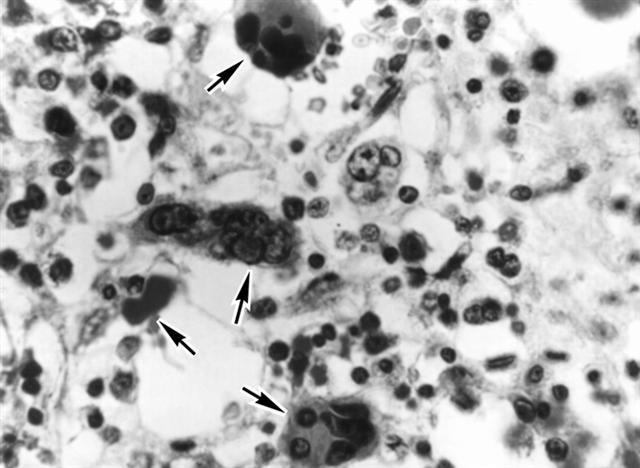

Рис. 4. Микропрепарат костного мозга при остром мегакариобластном лейкозе: стрелками указаны скопления атипичных мегакариоцитов. Окраска гематоксилином и эозином; ´400.